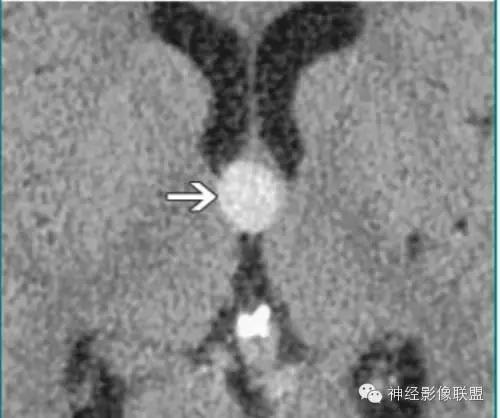

松果体囊肿